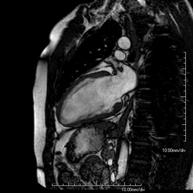

- RM Cardíaca

Es una prueba diagnóstica no invasiva que obtiene información morfológica y funcional del corazón y las estructuras adyacentes; de esta manera se pueden diagnosticar diferentes patologías congénitas y adquiridas, o bien realizar controles en pacientes con patología previa ya conocida. En la gran mayoría de casos es necesario el uso de contraste intravenoso (gadolinio) para completar el estudio, un tipo de contraste que raramente produce reacciones adversas. Durante la prueba, el técnico le pedirá varias veces que aguante la respiración durante 10-15 segundos para obtener las imágenes lo más claras posible. No se necesita preparación previa alguna por parte del paciente. La duración de la prueba es de aproximadamente 45-60 minutos. Está contraindicada en pacientes con marcapasos; el paciente debe avisar si es portador de implantes metálicos y/o clips quirúrgicos.

Es una prueba diagnóstica no invasiva, que obtiene información morfológica y funcional del corazón y las estructuras adyacentes. De esta manera, se pueden diagnosticar diferentes patologías congénitas y adquiridas, o bien realizar controles en pacientes con patología previa ya conocida. En la gran mayoría de casos es necesario el uso de contraste intravenoso (gadolinio) para completar el estudio, un tipo de contraste que raramente produce reacciones adversas. Durante la prueba, el técnico le pedirá varias veces que aguante la respiración durante 10-15 segundos, para obtener las imágenes lo más claras posible. No se necesita preparación previa alguna por parte del paciente. La duración de la prueba es de aproximadamente 45 - 60 minutos. Está contraindicada en pacientes con marcapasos, y el paciente debe avisar si es portador de implantes metálicos y/o clips quirúrgicos.